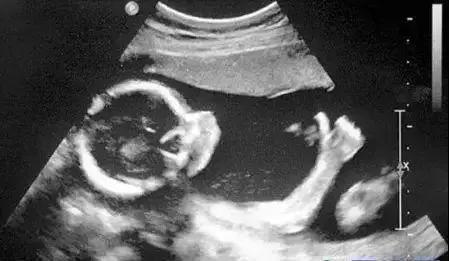

B超检查

敲一敲,听声波

孕妈妈们对B超不会陌生。它的原理是利用人体组织对超声波的回声不同,来判断正常组织和病灶的性质。B超和之前提到的三项检查有着较大的区别,但是因为B超机的探头掌握在B超医生的手上,指哪打哪,因此相对更依赖于检查医生的经验。

原理:用超声波穿透人体,当声波遇到人体组织时会产生反射波,通过计算反射波成像。

优点:多方位观察,实时成像。

缺点:超声受气体干扰很大,对于肠道等含气较多的器官,超声诊断准确率会降低,所以一般肠道检查使用肠镜。

B超对于人体管腔的液体流动和腹腔脏器检查的敏感性较高,我们常常遇到的胆囊结石、肾结石、血管狭窄、心脏功能等检查,都是B超的用武之地。B超技术便携,可以在床边,甚至在手术中使用。此外,B超是利用超声波成像,也没有所谓的辐射。所以孕妇多采用B超检查。